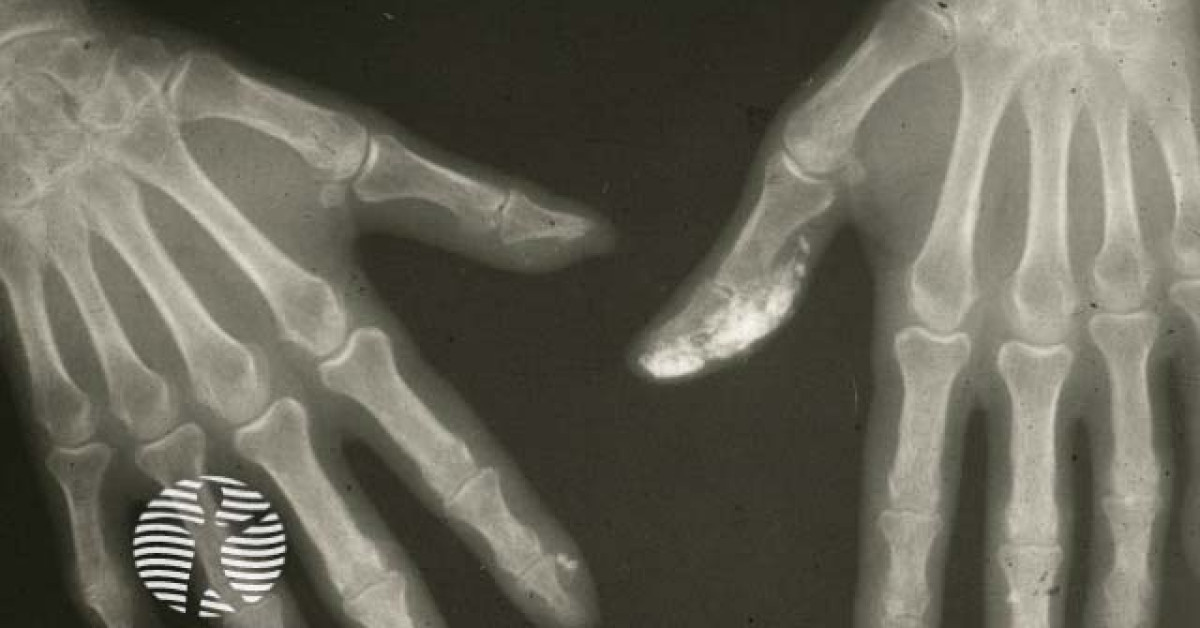

Xray calcium deposits fingers image What Causes Calcium Deposits In Fingers There are four different types of calcium deposits, each based on the cause of the condition:. The calcium deposits are hard. Web causes of calcification. Many factors play a role in calcification, including: Web calcification occurs when deposits of calcium form in the body. Web calcinosis cutis happens when calcium gathers in your skin, muscles, tendons, connective tissue, and. Calcium. What Causes Calcium Deposits In Fingers.

Figure 1 from Acute calcium deposits in the hand and wrist; comparison What Causes Calcium Deposits In Fingers Web the deposition of calcium in the skin, subcutaneous tissue, muscles and visceral organs is known as calcinosis. There are many types, each with their own causes, symptoms, and. Web calcium, or calcific, deposition disease in the form of acute calcific periarthritis of the hand and wrist is an uncommon entity that may. Many factors play a role in calcification,. What Causes Calcium Deposits In Fingers.

Figure 1 from Calcium deposits in the hand and wrist. Semantic Scholar What Causes Calcium Deposits In Fingers Web calcification occurs when deposits of calcium form in the body. Web calcinosis cutis happens when calcium gathers in your skin, muscles, tendons, connective tissue, and. Web causes of calcification. There are four different types of calcium deposits, each based on the cause of the condition:. Calcium metabolism disorders that cause. The calcium deposits are hard. There are many types,. What Causes Calcium Deposits In Fingers.